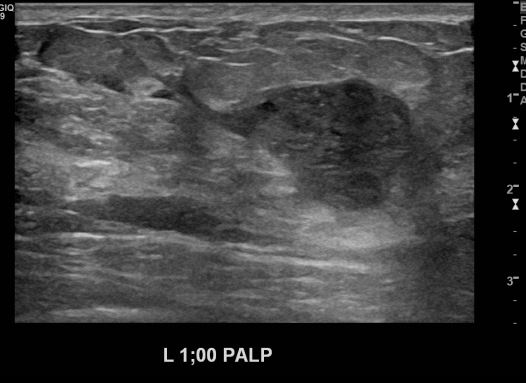

우측 유방의 멍울로 내원하신 40대 여성분으로 본원 초음파상 우측 유방에 의심스러운

멍울 조직검사 시행하여 우측 침윤성 유관암 진단 되었습니다.